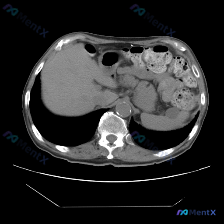

整理了一份有点「反转」的影像读片资料,感觉挺考验临床思维的,分享出来一起理理思路。 --- 一、影像基本信息 这是一张腹部CT横断面软组织窗图像,预设的观察焦点是「脾脏病变」。 二、结构化读片所见(客观描述) 按照读片常规扫了一遍全腹: 1. 肝脏、胆囊、胰腺:形态、大小、密度都正常,轮廓光滑,胰周...

今天看到一个很有意思的影像分析场景,整理一下思路和大家分享。 --- 病例背景 用户提供了一张腹部CT横断面(软组织窗),并直接询问:“图片中可见的特殊异常是什么?脾脏病变”。 影像核心表现 我先按标准流程梳理了这张CT的关键信息: 1. 脾脏:大小、形态正常,脾实质密度均匀,明确未见占位、梗死或异...